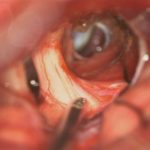

'24年10月

50代

頭蓋咽頭腫

頭蓋内腫瘍摘出術

No.’24_84 手術前1

No.’24_84 手術前2

No.’24_84 摘出 前

No.’24_84  摘出 中

No.’24_84 摘出 後